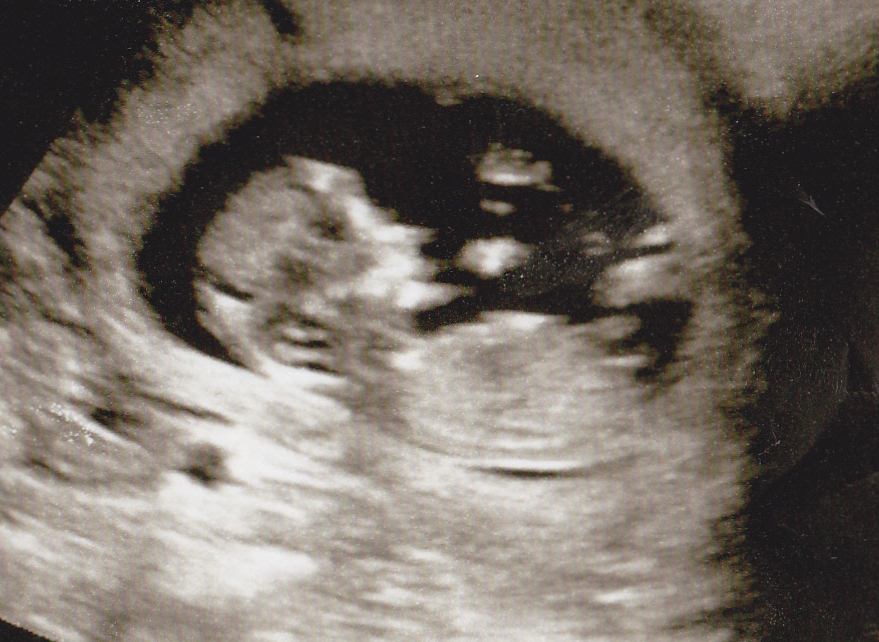

I dont know what to look for or if there is even a nub that can be seen on this pic but would love to know what your guesses are boy or girl??

Attachment 15410